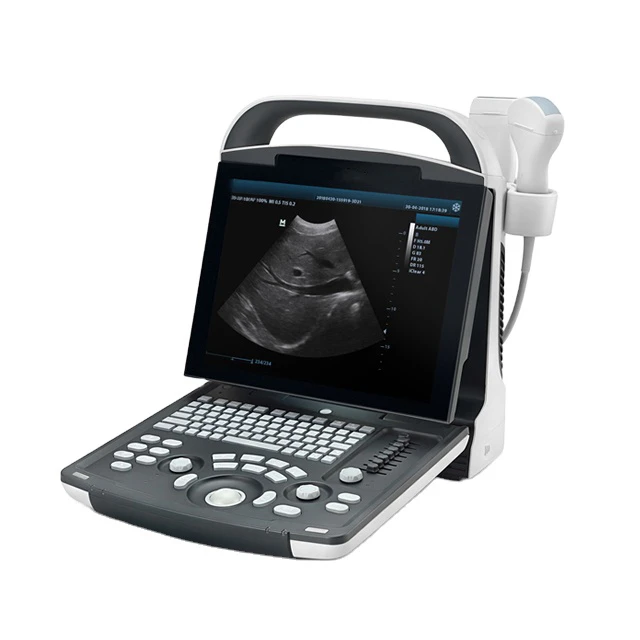

Portable Ultrasound Machine Mindray DP-10

12.1" LED Monitor

8-Segment

Light and compact

1 PCS

Abdomen, OB, GYN, Cardiology, Urology, Vascular

320Gb

Black and white